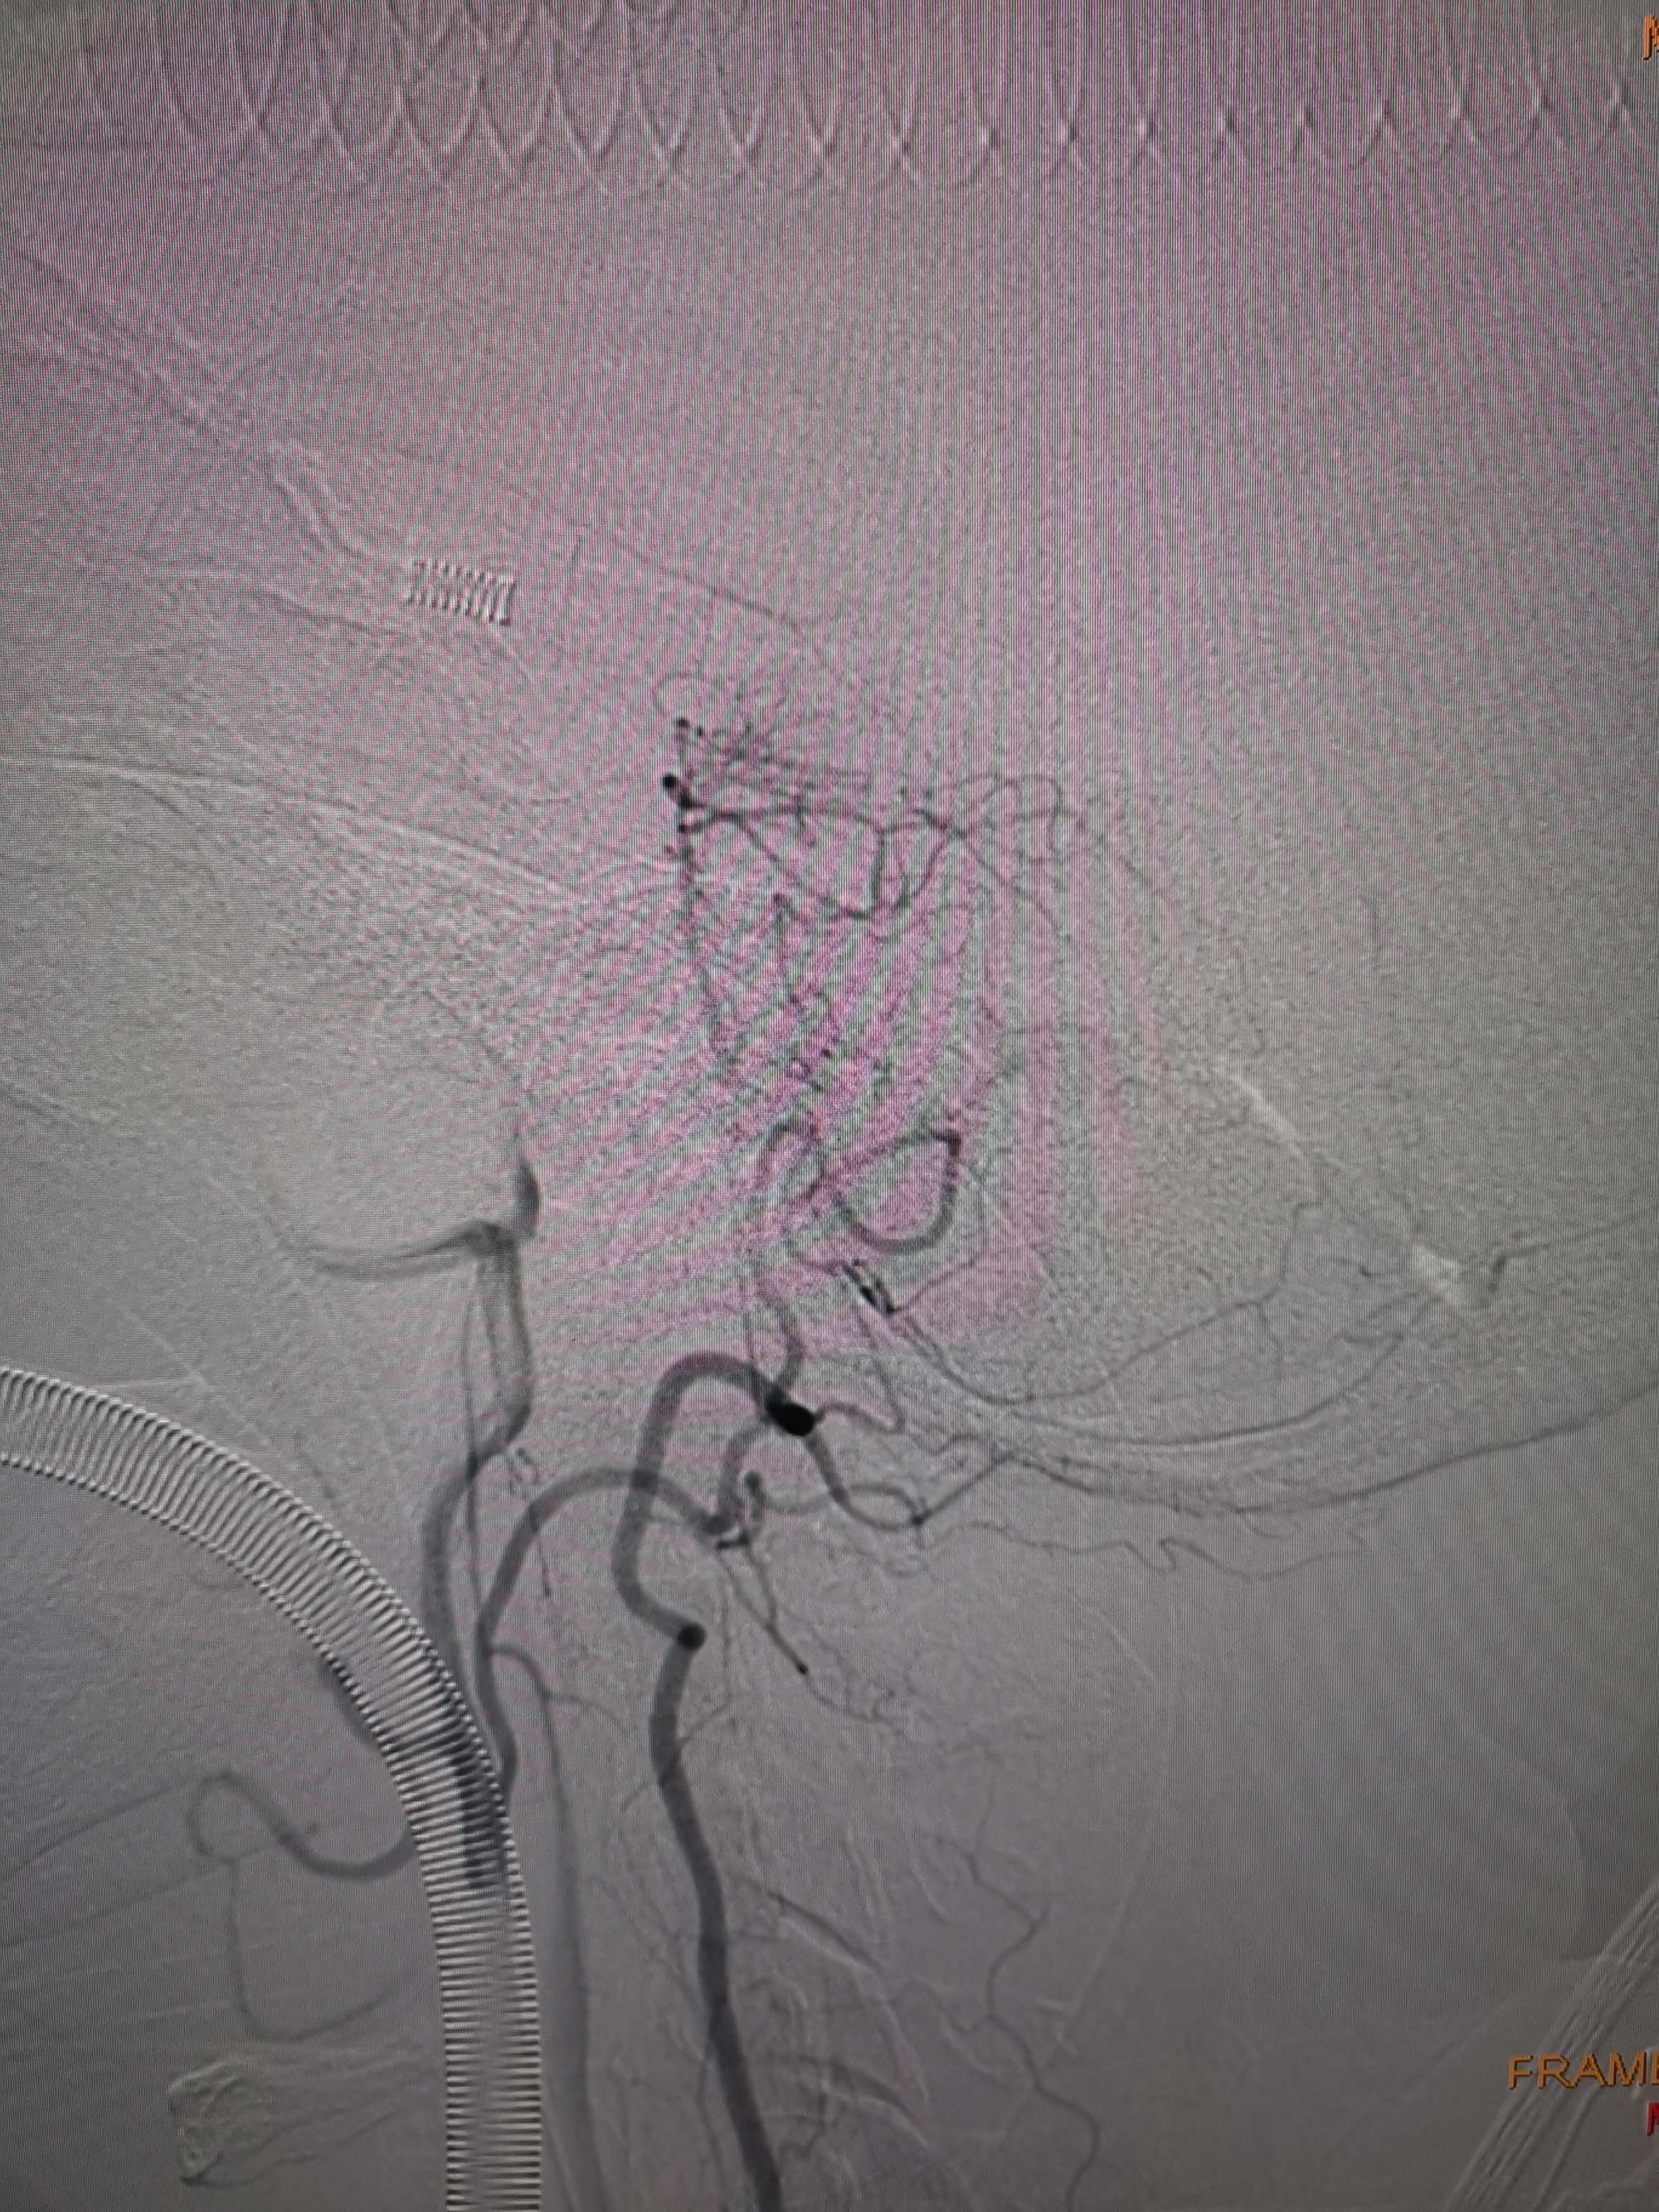

手术过程

在微导管支撑下先将微导丝和微导管穿过闭塞段,微导管超选造影证实位于基底动脉真腔后更换300cm外周交换导丝,撤出微导管后按从小到大,从远到近的原则行球囊扩张,本例手术选择了1.5✖️15、2.0✖️20、2.5✖️20球囊进行扩张,扩张满意后植入Enterprise支架,手术结束。

术后造影见左侧椎动脉闭塞段管腔恢复正常直径,远端血运良好。